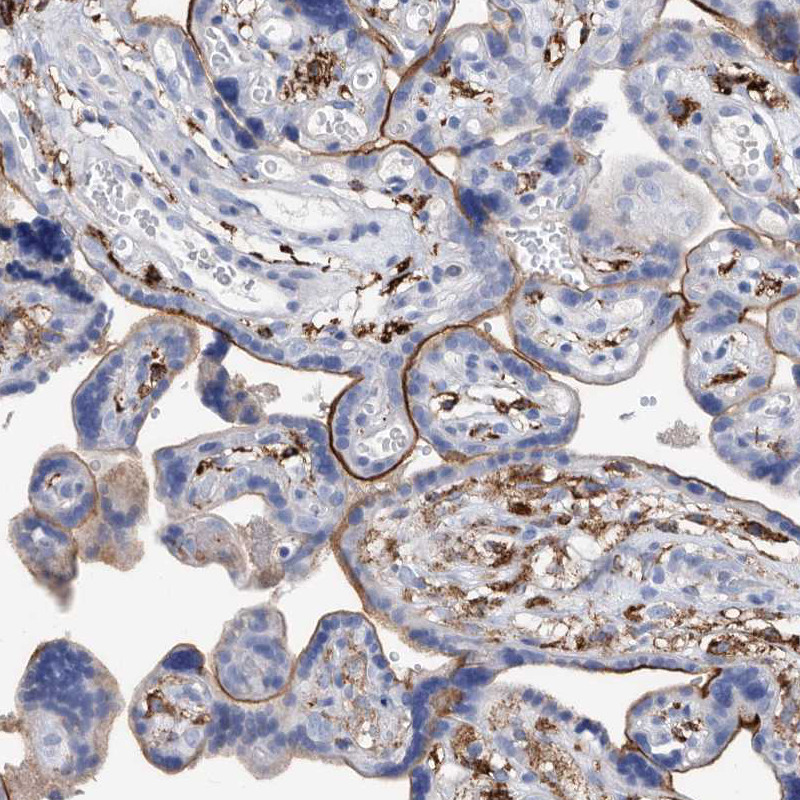

Immunohistochemical staining of human placenta shows membranous cytoplasmic positivity in macrophages and in trophoblastic cells.